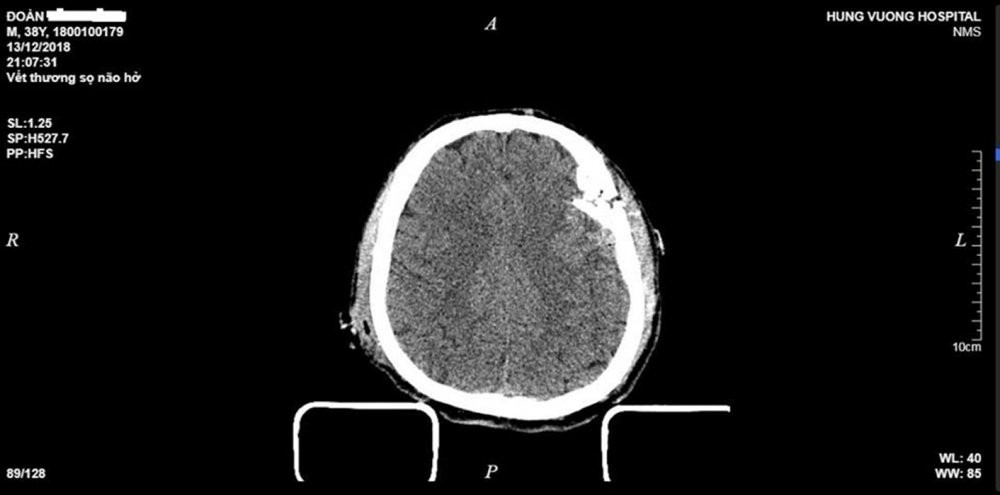

Hình ảnh vết thương sọ não hở của bệnh nhân Đ.V.T. (Ảnh: Bệnh viện cung cấp)

Qua hình ảnh phim chụp cắt lớp vi tính cho thấy, hình ảnh vỡ lún phức tạp xương trán đỉnh thái dương trái, tụ máu ngoài màng cứng, dập não đa ổ thái dương trái, xuất huyết dưới nhện.

Bệnh nhân Đ.V.T. (38 tuổi, trú tại Sơn Dương, Tuyên Quang) bị tai nạn giao thông, nhập viện trong tình trạng lơ mơ, vết thương vùng trán đỉnh ~12cm, bờ vết thương nham nhở, chảy máu nhiều, lộ mảng xương sọ vỡ lún, tổ chức não đùn ra ngoài, đồng tử trái giãn 3,5mm, phản xạ ánh sáng kém.